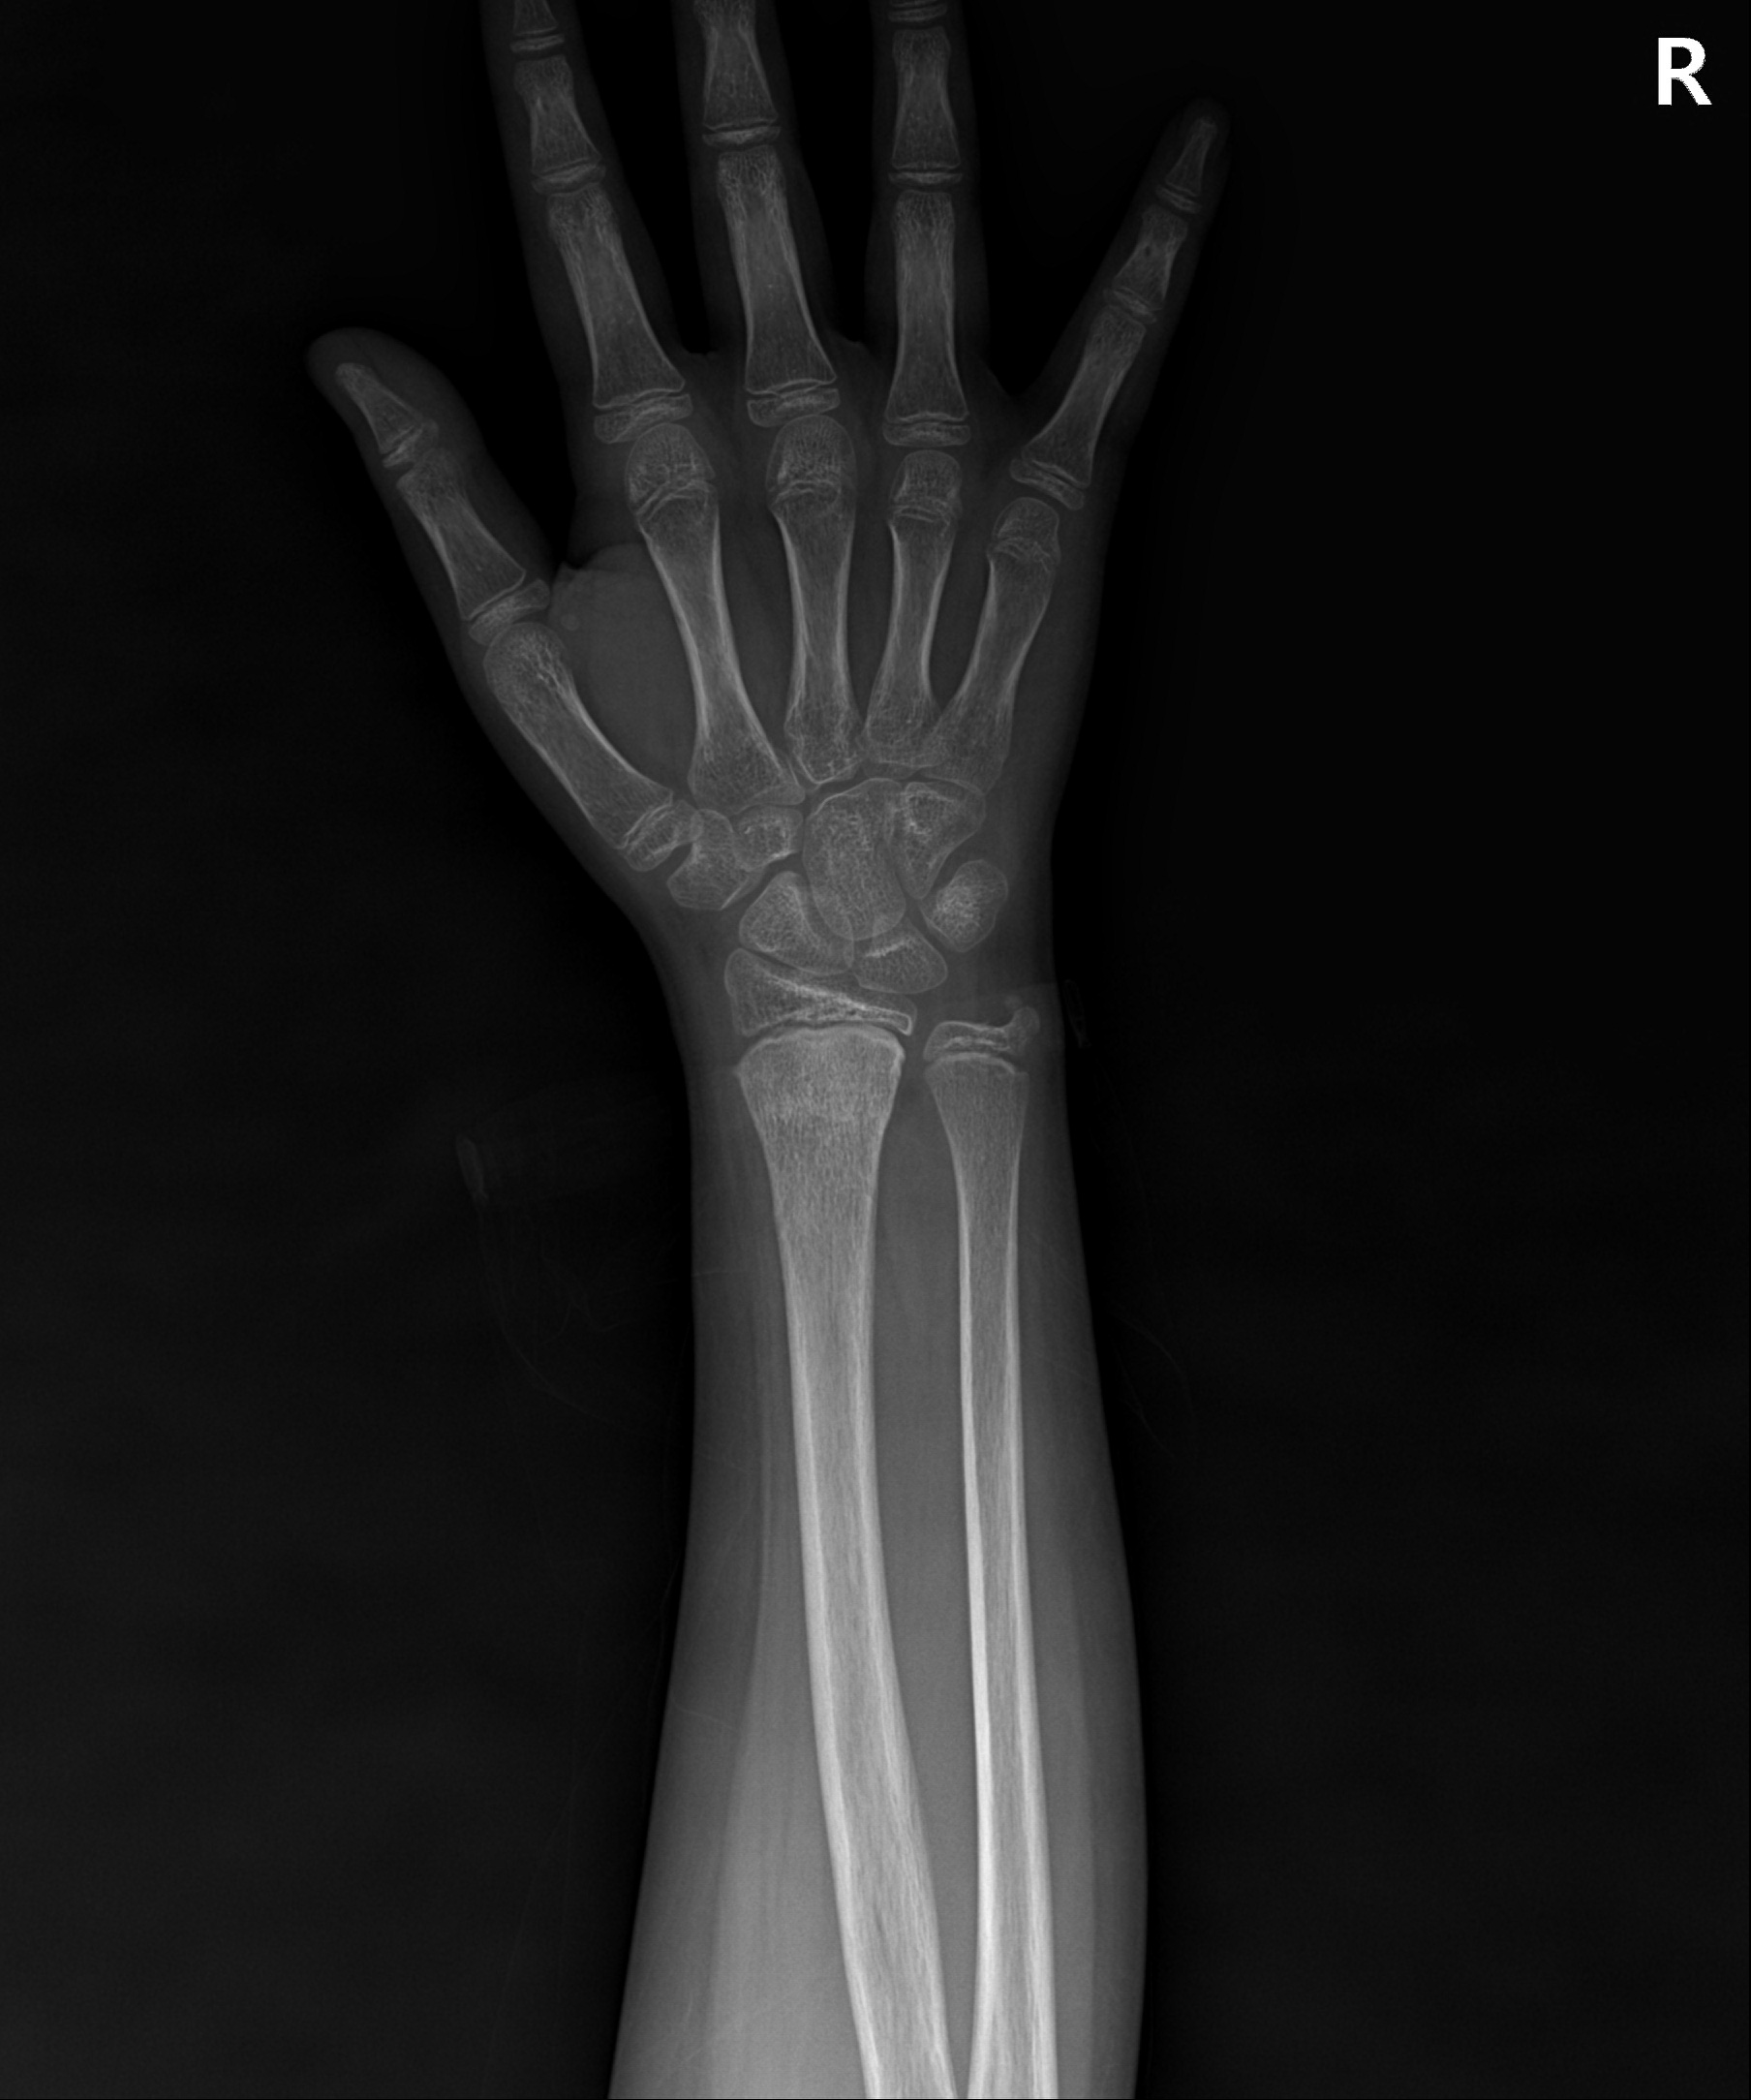

손목 골절 및 손가락 골절

대부분 손을 짚고 넘어지면서 발생하는 골절이고 다치면서 손등 쪽 뼈가 심하게 분쇄되는 경우가 많습니다.

골절 초기나 아니면 지연성으로 골절편이 손등 쪽으로 휘어져 변형이 발생하기 쉽습니다.

손목&손가락 골절에서 발생하는 문제점

□ 골절을 유합 시키기 위해 장기간 깁스를 할 경우 손목 관절이나 손가락 강직 발생

□ 손목 관절을 정확히 정복하지 못할 경우 외상성 관절염 발생 위험 높음

손목 골절

2023.01.04

2023.03.20